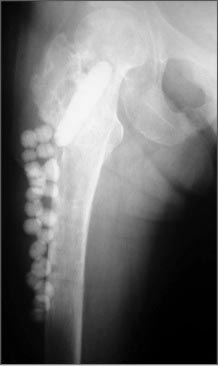

Здесь пример лечения антибиотическими бусами и форма для бус!

Вложение не в текстовом формате было извлечено…

Имя     : Hip Infection 2.jpg

Тип     : image/jpeg

Размер  : 18938 байтов